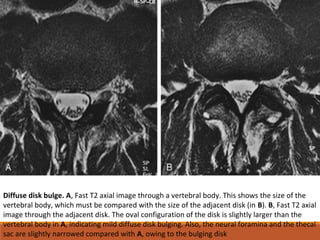

Diffuse disk bulge. A, Fast T2 axial image through a vertebral body. This shows the size of the

vertebral body, which must be compared with the size of the adjacent disk (in B). B, Fast T2 axial

image through the adjacent disk. The oval configuration of the disk is slightly larger than the

vertebral body in A, indicating mild diffuse disk bulging. Also, the neural foramina and the thecal

sac are slightly narrowed compared with A, owing to the bulging disk